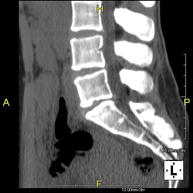

Lumbar spine CT

Radiological test that provides high definition anatomical images of the lumbar vertebrae using CT (Computed Tomography) equipment. Indicated for: lower back pain with or without radiation to the legs, difficulty walking, trauma.